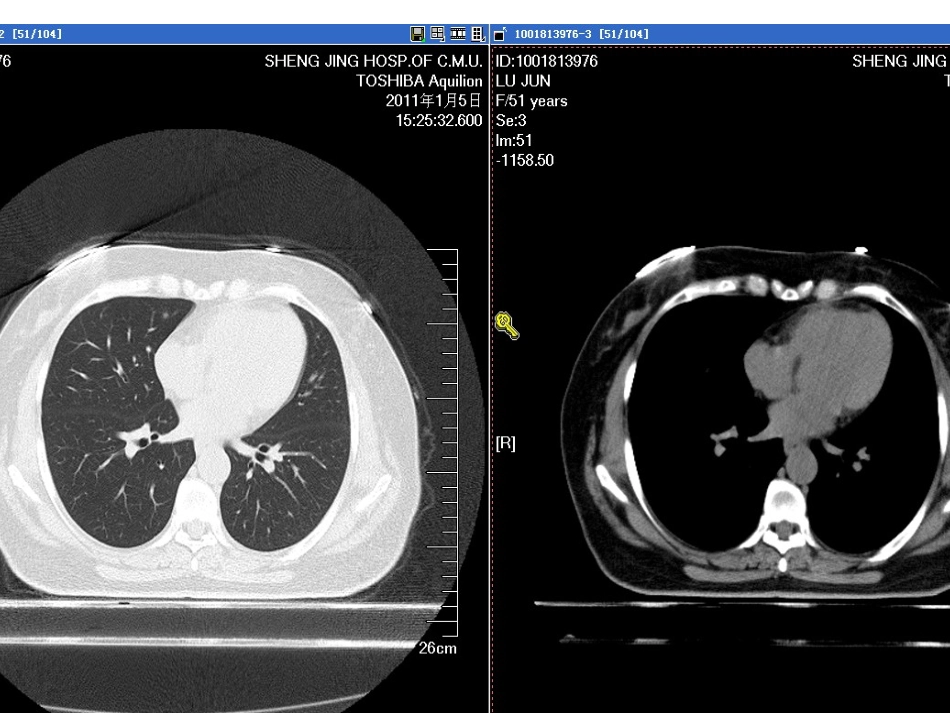

肺癌筛查指南NationalComprehensiveCancerNetworkVersion1.2012是否为恶性?会不会恶变?需要复查吗?美国国家综合癌症网(NCCN)指出,在美国和世界其它国家,癌症相关的死亡数量中,肺癌是最主要的死因。据估计2011年,在美国,肺癌将导致156900人死亡(男性85600,女性71300)。肺癌的5年生存率仅约15.6%,一部分原因是大部分病人在初次就诊时已是肺癌晚期。对子宫颈癌、结肠癌、乳腺癌的筛查以改善疾病预后,这些成功经验是发展一种有效的肺癌筛查测验的推动力。理想目标是,有效的筛查会早期检测出肺癌,并在患者出现症状前,这时治疗更可能有效,减少死亡率。目前,大部分肺癌是在患者有症状时作出临床诊断,如出现咳嗽、胸痛、体重减轻。很不幸,有这些症状的患者通常是晚期肺癌。美国NCCN(国家综合癌症网)于2011年10月底首次发布了肺癌筛查指南,指南的发布是基于新英格兰医学杂志(NEJM)于2011年8月发表的美国国立肺癌筛查研究(NLST)的结果。该研究对高危人群应用低剂量螺旋CT(LDCT)做每年常规检查,结果发现,与胸片体检相比,LDCT体检可以使肺癌死亡率降低20%,使任何原因死亡率降低7%。基于这一结果,指南中明确将LDCT作为肺癌筛查手段,并对LDCT上的不同发现做出了不同的处理指南。总的来说,NCCN指南建议对肺癌高危人群每年进行肺部低剂量螺旋CT检查。高危人群是指:A.55-74岁,正在吸烟或者戒烟少于15年,并且吸烟指数大于30包年。B.年龄≥50岁,吸烟指数≥20包年,并且合并下列情况之一者:肿瘤病史;肺病史;家族中有肺癌患者;住所氡暴露和致癌物质的职业性暴露(包括砷、铬、石棉、镍、镉、铍、二氧化硅和柴油烟气)。以上肺癌高危人群建议每年行低剂量螺旋CT(LDCT)检查,最少3年(最佳持续年限尚不清楚)。中危人群:年龄≥50岁,吸烟指数≥20包年,或有二手烟暴露,没有附加的危险因素。低危人群:年龄<50岁和/或吸烟指数<20包年。以上不推荐常规肺癌筛查根据CT检查结果不同采取不同的处理措施A.未发现肺部结节:每年LDCT检查,至少持续3年(最佳持续年限尚不清楚)。B.发现肺部实性或部分实性结节(无良性钙化、脂肪或炎性表现的结节):a.≤4mm,每年LDCT检查,至少持续3年(最佳持续年限尚不清楚)b.>4—6mm,6个月后复查LDCT,如无增长,12个月后复查LDCT,仍无增长,每年复查LDCT,至少2年(最佳持续年限尚不清楚)12个月后复查,如有增长,推荐外科切除c.>6—8mm,3个月后复查LDCT,如无增长,6个月后复查LDCT,无变化则12个月后复查LDCT,仍无变化,每年复查LDCT,至少2年(最佳持续年限尚不清楚)。6个月后复查LDCT,如有增长,推荐外科切除d.>8mm,考虑PET/CT检查,如怀疑肺癌,手术或活检。活检结果不是肺癌,每年复查LDCT,至少2年(最佳持续年限尚不清楚)证实肺癌,参照NCCN非小细胞肺癌指南。不考虑肺癌,动态观察同上。以上情况在动态观察中,如发现结节增长,建议手术切除。e.发现支气管内结节,1个月后复查LDCT,出现剧烈咳嗽应立即复查。如无消退,做纤维支气管镜检查明确。C.发现肺部磨玻璃影(GGO)或其他非实性结节(无明确良性指证):a.<5mm,12个月后复查CT,如稳定,每年LDCT检查,至少持续2年(最佳持续年限尚不清楚)。增长和/或变为实性或部分实性:3-6个月后复查LDCT或考虑外科切除。活检结果不是肺癌,每年复查LDCT,至少2年(最佳持续年限尚不清楚)。证实肺癌,参照NCCN非小细胞肺癌指南。b.5-10mm,6个月后复查CT,如稳定,每年LDCT检查,至少持续2年(最佳持续年限尚不清楚)。增长和/或变为实性或部分实性:外科切除。活检结果不是肺癌,每年复查LDCT,至少2年(最佳持续年限尚不清楚)。证实肺癌,参照NCCN非小细胞肺癌指南。c.>10mm,3-6个月后复查LDCT,如稳定,可以6-12个月后复查LDCT,或者活检或手术切除。活检结果不是肺癌,每年复查LDCT,至少2年(最佳持续年限尚不清楚)。证实肺癌,参照NCCN非小细胞肺癌指南。增长和/或变为实性或部分实性:外科切除。以上动态观察中如果发现结节增大或者实性变,除直径<5mm者可以考虑3-6个月动态复查LDCT外,其他均应手术切除。筛查结果评估每年或随访的...